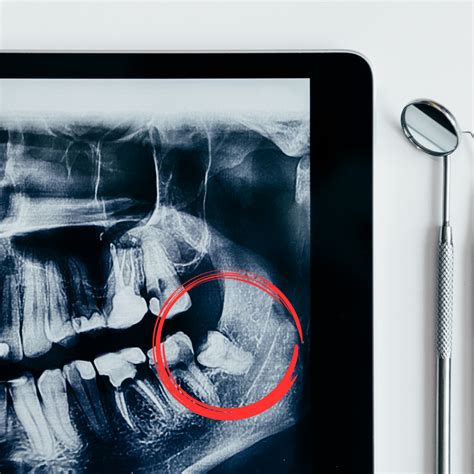

Antes de proceder con cualquier tratamiento de ortodoncia, es fundamental realizar un estudio completo de la boca del paciente. Este estudio incluye radiografías panorámicas y de perfil, fotografías intraorales y escaneado intraorales (antiguos modelos de escayola de la boca). Este análisis detallado ayuda al ortodoncista a determinar si es necesario realizar extracciones dentales para lograr los resultados deseados.

Tradicionalmente, en ortodoncia se suelen extraer los premolares para crear espacio y alinear correctamente los dientes en la boca. En adultos con apiñamiento inferior severo y mordida bien engranada, a veces optamos por extraer un incisivo inferior. En cualquier caso, la decisión final sobre qué pieza dental extraer va a depender del caso particular del paciente y de los objetivos del tratamiento ortodóncico.